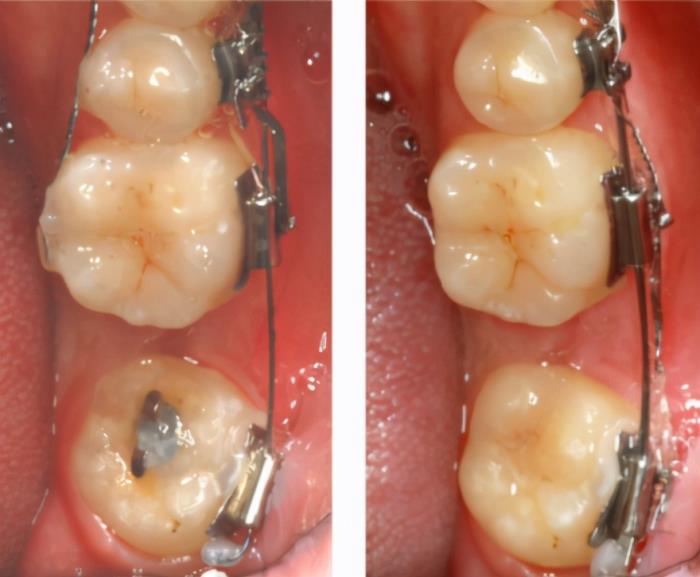

可用于牵引的智齿。

如果的智齿形状正常但没有完全萌出,而智齿前面的第二磨牙损坏非常大,需要进行根管治疗甚至打桩做冠时,可以咨询正畸医生,看是否可以拔除龋坏面积大的第二磨牙,然后用正畸的方式把智齿牵引到第二磨牙的位置。如果可以,是不用拔除的!

形状正常,可用于牵引的智齿

同样是需要智齿形状正常的智齿,可以没有完全萌出。智齿前面的第二磨牙健康,但六龄齿损坏大无保留价值。可咨询正畸医生,把拔除六龄齿,然后用正畸的方式把智齿第二磨牙牵引到六龄齿的位置,而智齿则牵引到第二磨牙的位置,以保证可以正常行驶功能。

形态正常,可用将智齿牵引到缺牙位置。

智齿没有完全萌出,但形态是正常的,而智齿前面的某个磨牙先天缺失、乳牙滞留时,同样是可以咨询正畸医生,拔掉乳牙,然后用牵引的方式将智齿牵引到拔牙后的位置上。